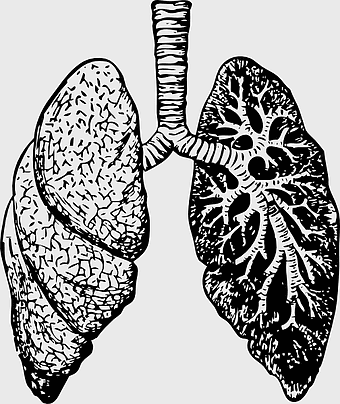

lung anatomy sketch, human respiratory system drawing, black and white lung illustration, monochrome human lungs, pulmonary organ diagram, breathing system art, medical illustration of lungs -